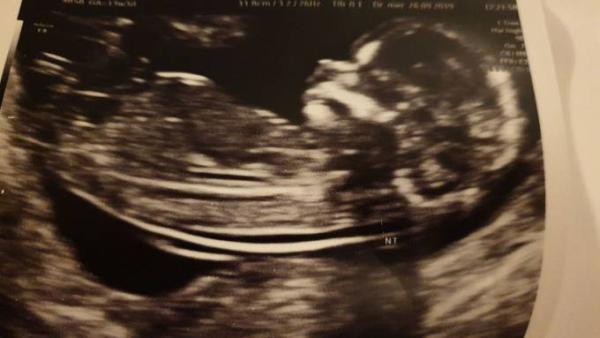

...war total aufgeregt. Aber alles wie es sein soll. Laut US ist das Risiko für Trisomie o.ä. sehr unwahrscheinlich. Die Ärztin war ganz begeistert wss für schöne Bilder sie machen konnte :D Zum Schluss schaute sie ganz lange zwischen die Beinchen und meinte das da der Zipfel fehlt und sie momentan zu einem Mädchen tendieren würde..aber alles mit Vorsicht genießen. Der mittlere war bei 12+ 2 angeblich auch ein Mädchen...damals konnte ich ihr das aber nicht glauben. Aber wie gesagt..nach 2 Jungs wäre Rosa ein Traum..und diesmal ist alles anders..ich habe dieses Mädchengefühl :D Mal schauen. In 14Tagen ist die wunschsono wo mein Mann das Böhnchen das erste mal Live sieht. .da sieht man es sicher besser. Drückt mir die Daumen.

Bild zu Heute Ersttrimesterscreening - Forum für April - Mamis

Was für ein schönes Bildchen

Ach wie schön. Es freut mich sehr, dass alles gut ist Das Bild ist wirklich Zucker ich bin immer wieder erstaunt, was man schon alles darstellen kann